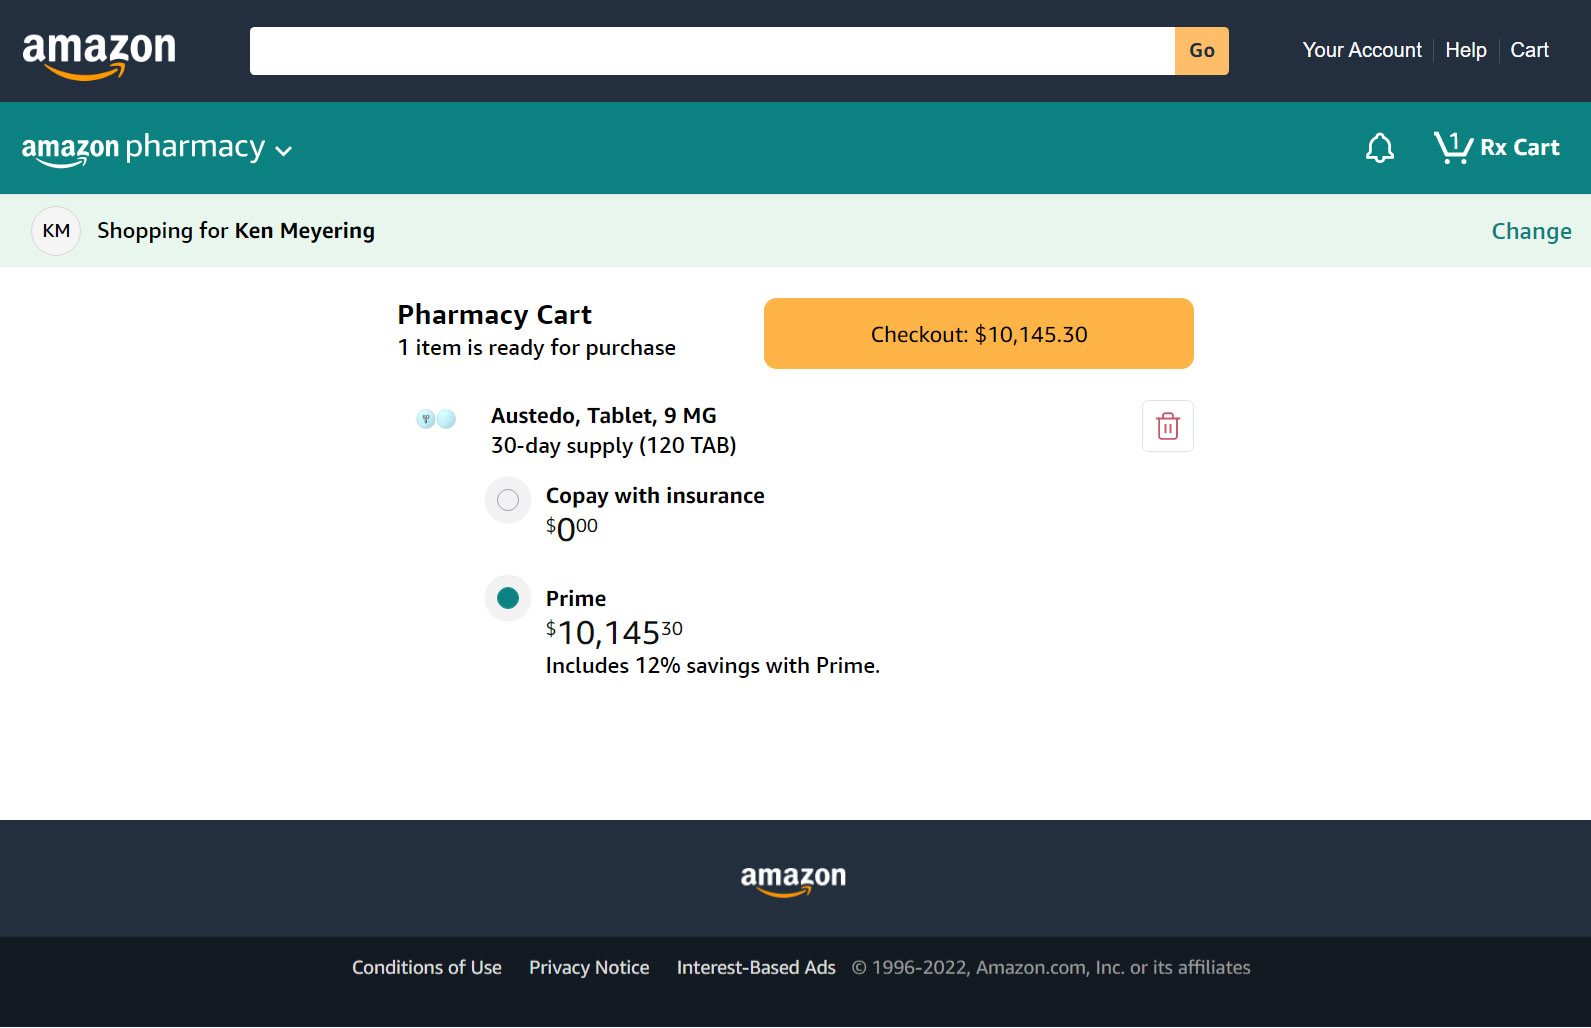

https://media.define.com/Kens-Austedo-Prescription-Price.jpg